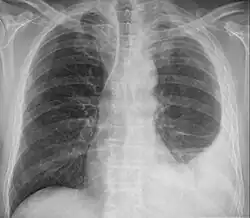

Die Diagnose wird meist erst in einem fortgeschrittenen Stadium gestellt. Zur Diagnosesicherung wird ein Röntgen, CT oder MRT der Lunge und eine Bronchoskopie zur differenzialdiagnostischen Abgrenzung eines Bronchialkarzinoms durchgeführt. Bei der Pleurapunktion können in 30–50 % der Fälle Tumorzellen nachgewiesen werden; zu beachten ist hierbei das etwa 20%ige Risiko der Bildung von Metastasen im Stichkanal durch die direkte Verschleppung von Tumorzellen (= Impfmetastasen). Eine Pleurapunktion alleine ohne Nachweis von Tumorzellen schließt ein Pleuramesotheliom nicht aus. Die höchste Aussagekraft besitzt die Thorakoskopie mit Biopsie, welche in Zweifelsfällen durchgeführt werden muss.